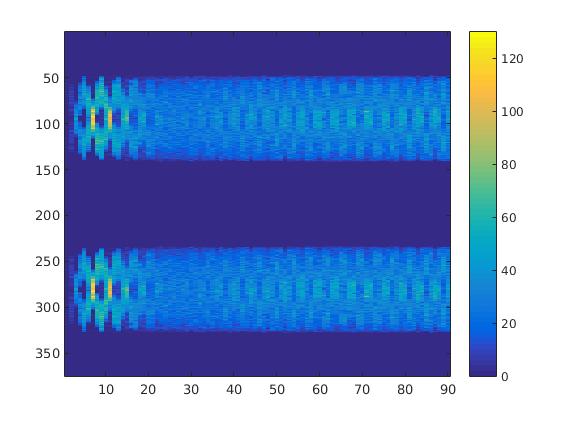

To simulate the synthesized SPECT data, we apply a Radon transform assuming a double detector gamma camera, which counts photons from two opposing projection angles per time step. For the more simple data set, we let the camera rotate clockwise around two degree per time step, in case of the complex data set we used modified projection angles, i.e. the camera alternatingly projects from an angle of i and 45+i degrees, in order to simplify the reconstruction. Each collimator consists of detector bins, so we obtain data points per time step and projection angle. The resulting sinogram data of the two underlying data sets are shown in figure 3.

In two different tests we fixed the number of events counted by the detector equal to (resp. ) times the average concentration in one pixel. The resulting sinogram images of the accumulated counts in each bin are shown in figure 9.